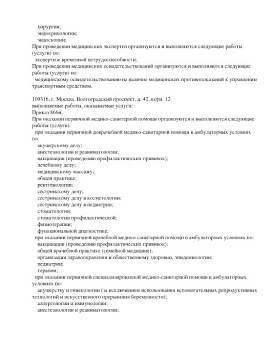

Лицензии